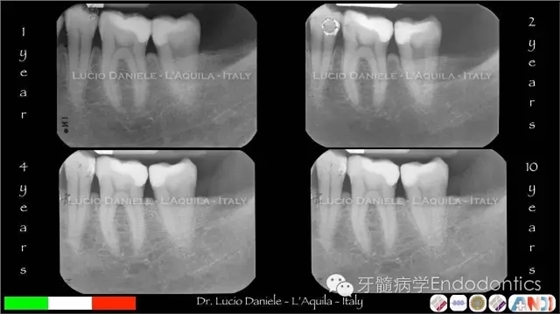

圖5.隨訪2年、4年、10年